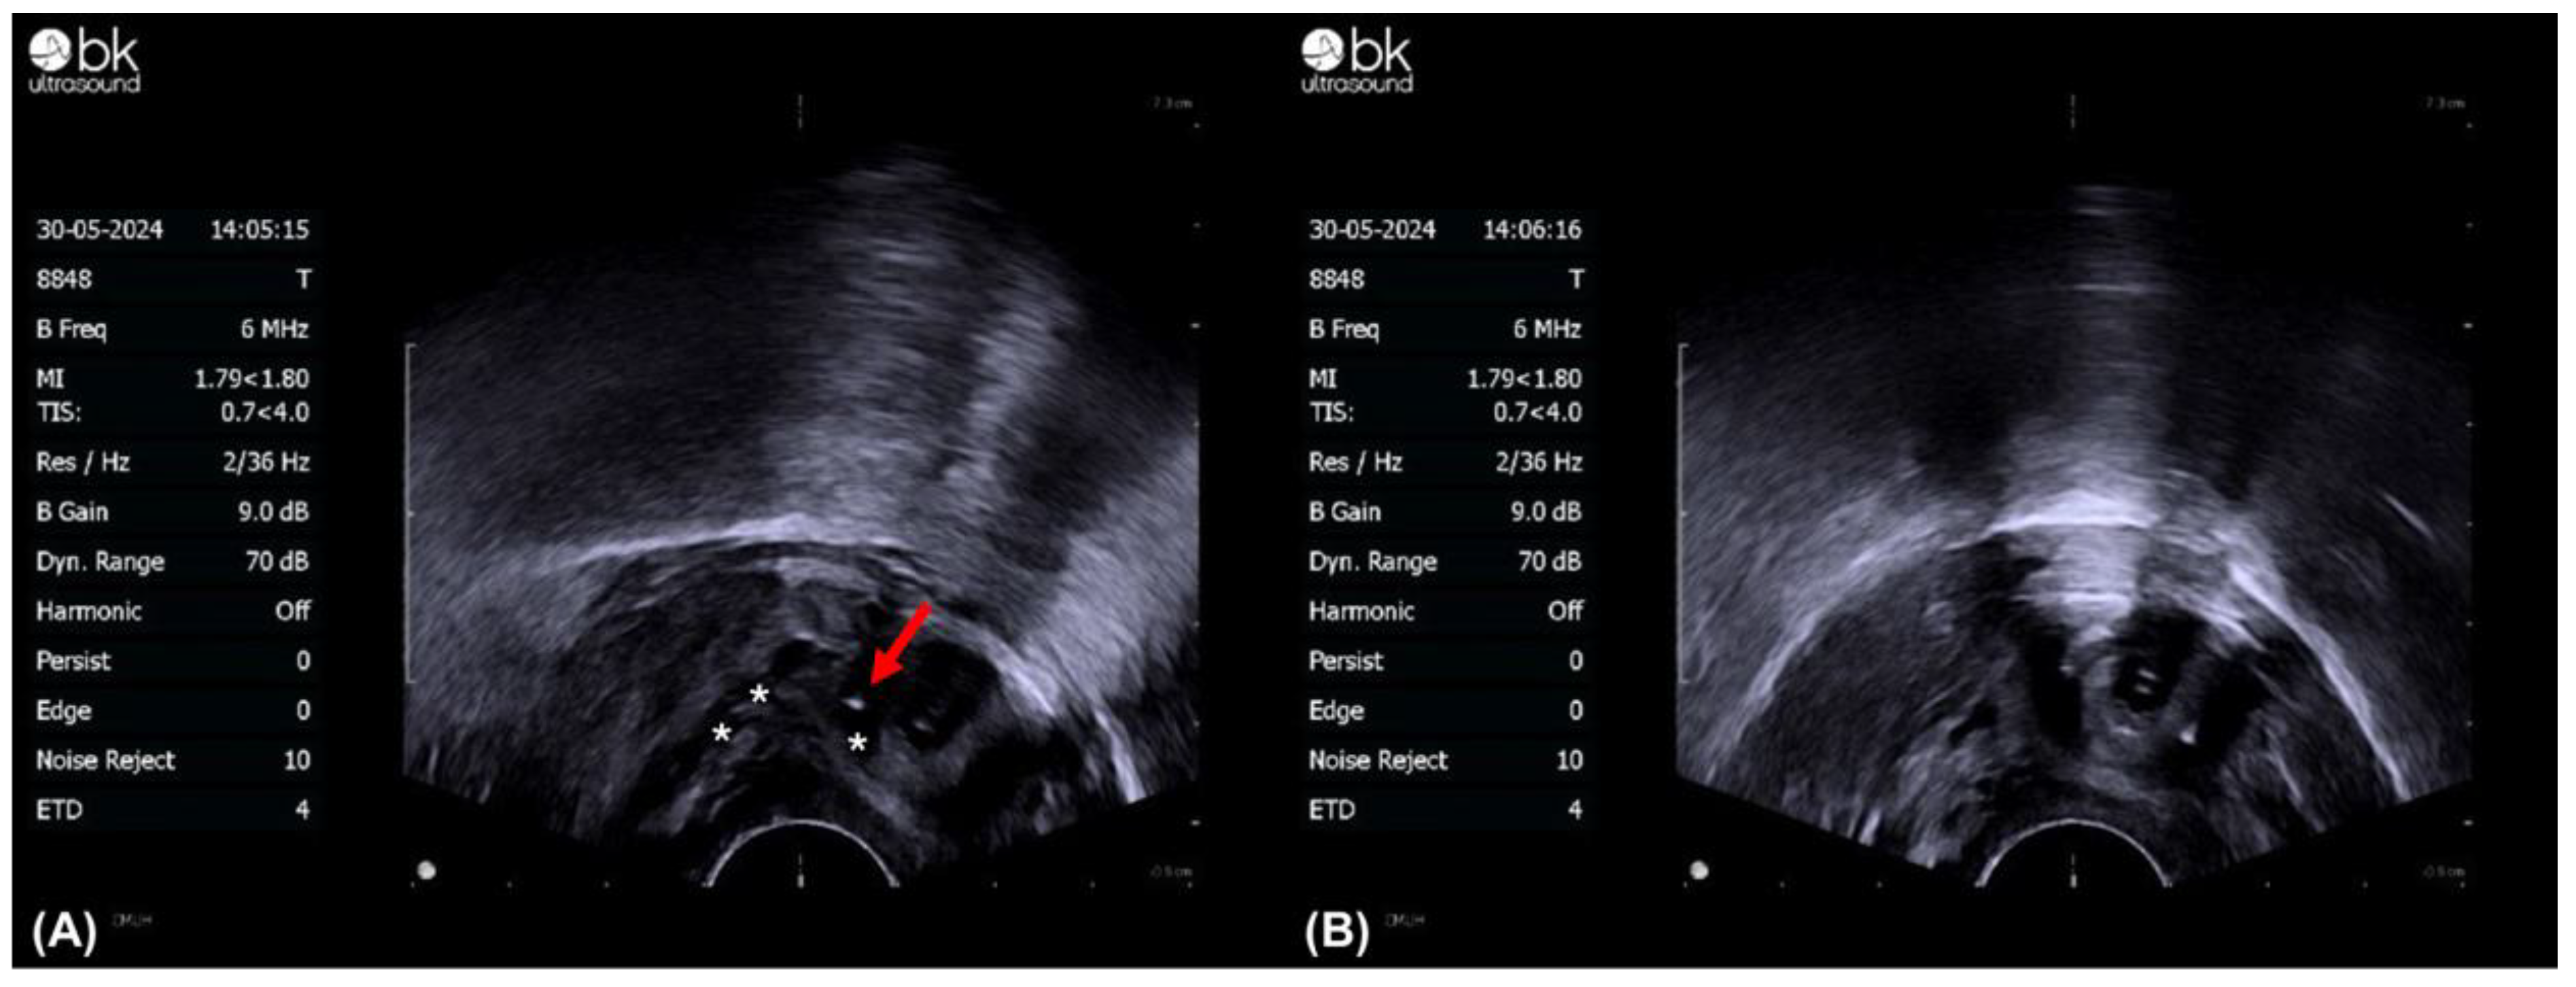

5.2. A Novel Treatment: Surgical Treatment with a Combination of Transvaginal Ultrasound-Guided BoNT-A Injection and TUI-BN